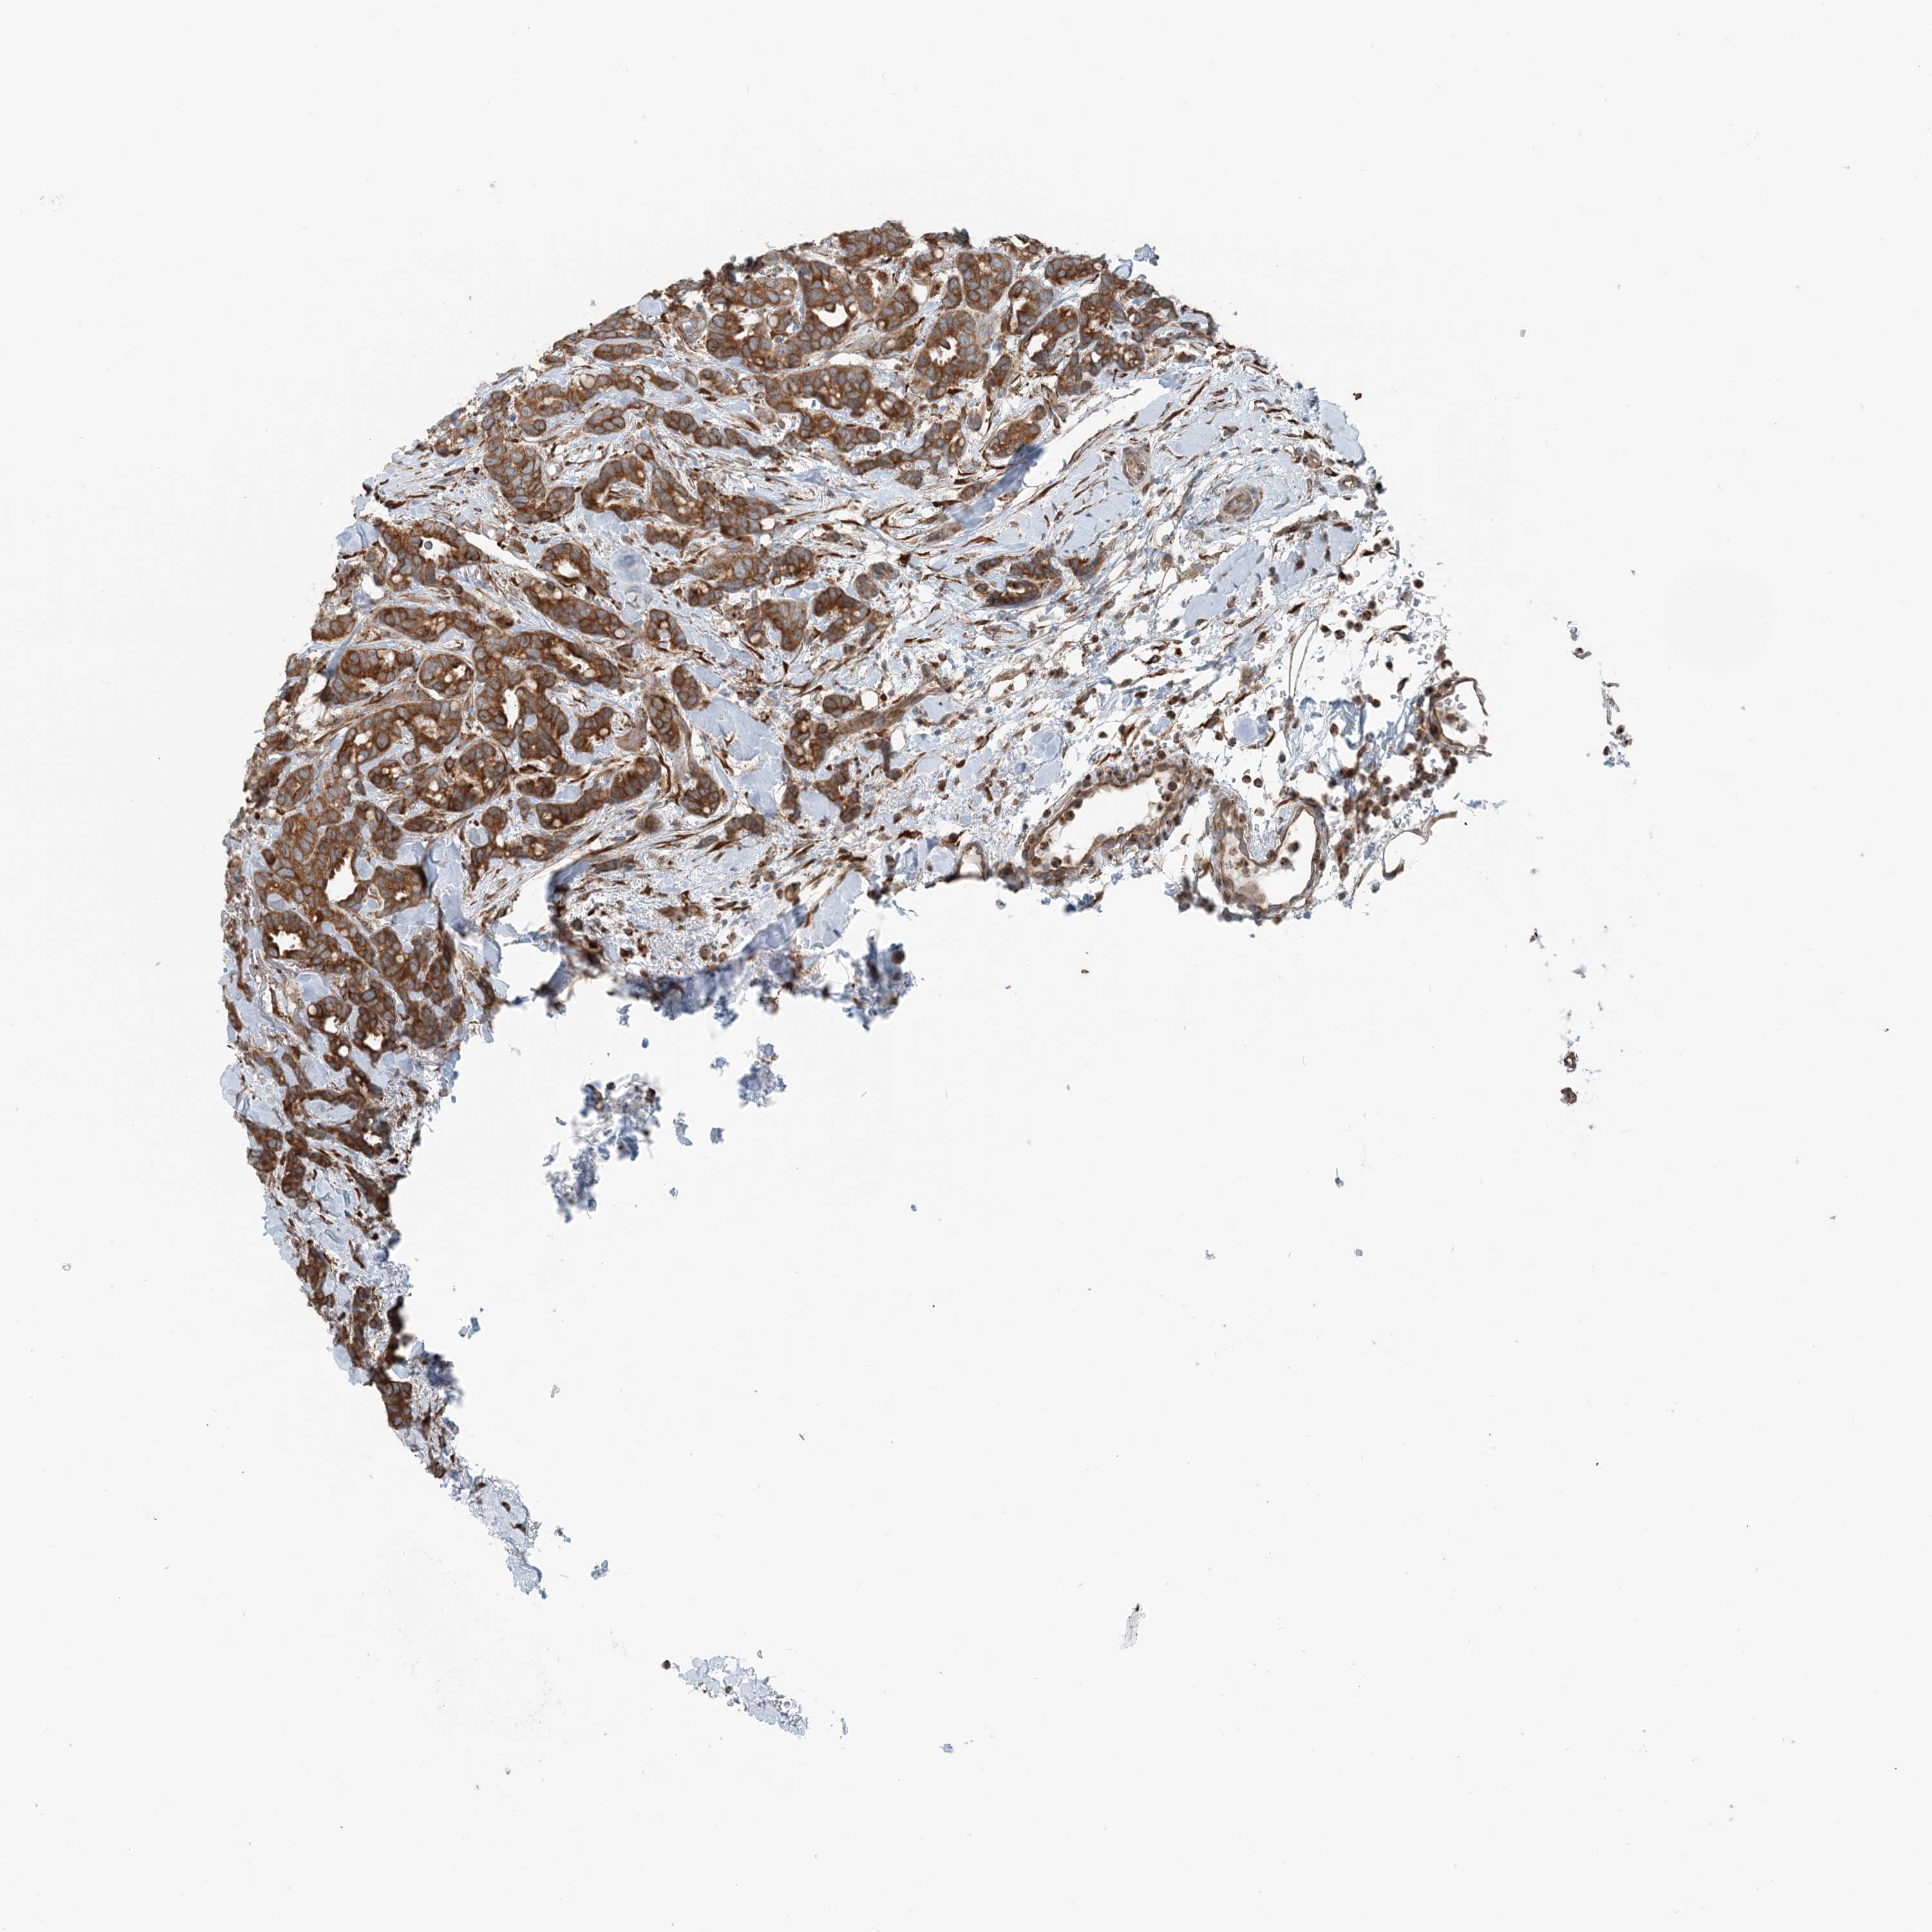

CANCER BREAST CANCER Show tissue menu

BRCA TCGA BRCA VALIDATION PROTEIN EXPRESSION